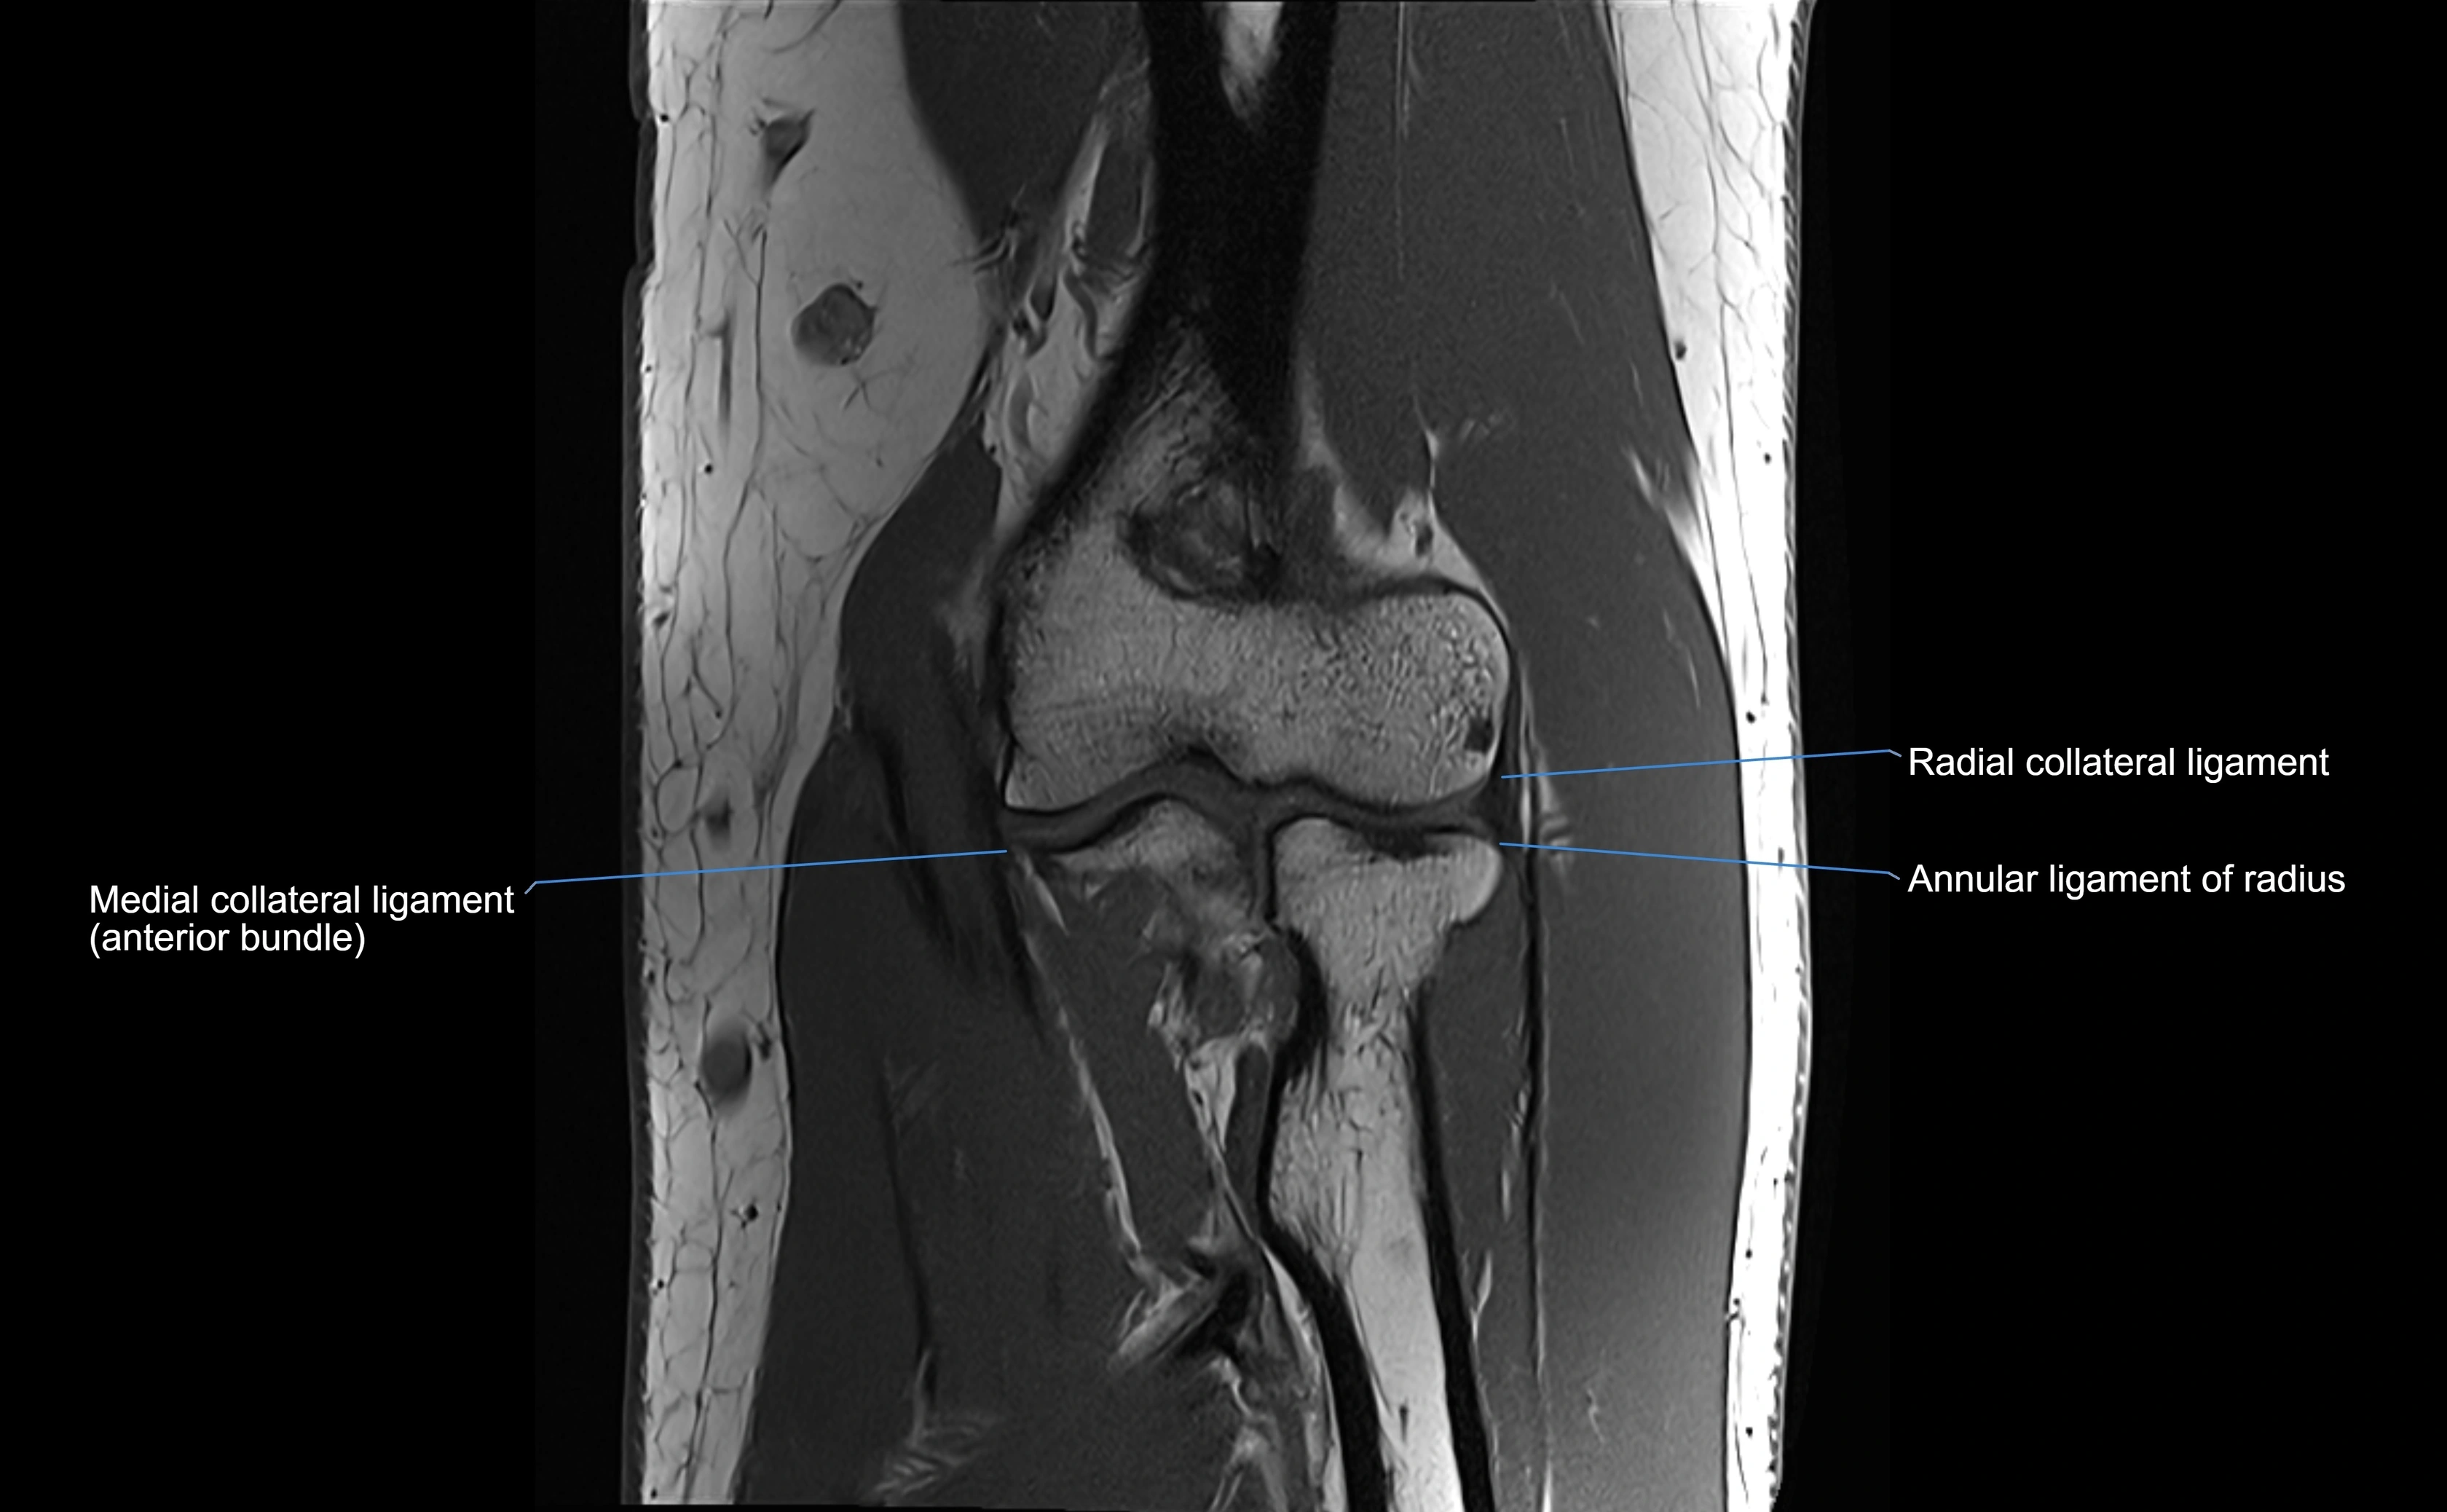

Annular ligament of radius

The annular ligament of the radius is a strong, circular band of fibers that encircles the head and neck of the radius, holding it securely against the radial notch of the ulna. It forms part of the proximal radioulnar joint, permitting smooth rotation of the radius during pronation and supination of the forearm.

The ligament acts like a collar or loop, maintaining radial head stability while allowing rotation. It is essential for forearm motion, elbow stability, and load transmission from the radius to the ulna and humerus.

Origin, Course, and Insertion

• Origin: Arises from the anterior margin of the radial notch of the ulna.

• Course: Forms a strong circular band that wraps around the radial head and neck, maintaining them within the radial notch.

• Insertion: Attaches to the posterior margin of the radial notch, completing a fibrous ring around the radial head.

• The inner surface of the ligament is lined with synovial membrane, allowing frictionless rotation.

Relations

• Superiorly: Blends with the capsule of the elbow joint.

• Inferiorly: Supported by the quadrate ligament at the neck of the radius.

• Medially: Attached to the ulnar radial notch.

• Laterally: In contact with the radial head and its articular cartilage.

• Anteriorly: Related to the radial collateral ligament of the elbow.

• Posteriorly: Continuous with the elbow joint capsule.

MRI Appearance

T1-weighted images:

• Ligament: low signal intensity (dark), appearing as a continuous band around the radial head.

• Adjacent fat and marrow: bright, creating contrast with the ligament.

• Thickening or disruption indicates injury or fibrosis.

• Joint capsule and synovium seen as thin low-signal lines contiguous with ligament margins.

T2-weighted images:

• Ligament: low signal (dark) with clear delineation from joint fluid.

• Fluid or edema: bright hyperintense, separating or surrounding the ligament in partial tears.

• Complete tear: discontinuity or non-visualization of ligament fibers, often with joint effusion.